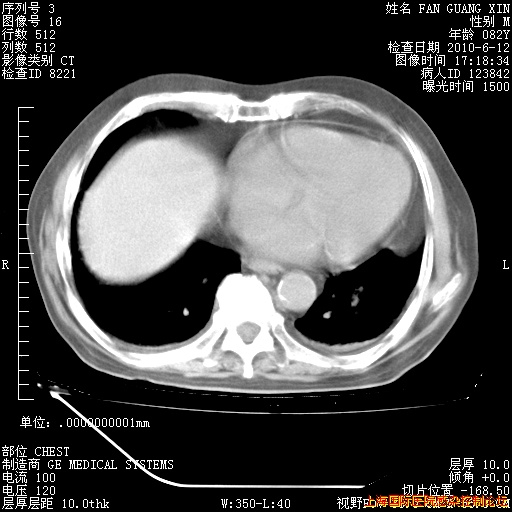

补发6月12日肺部CT肺窗

6月12日肺窗